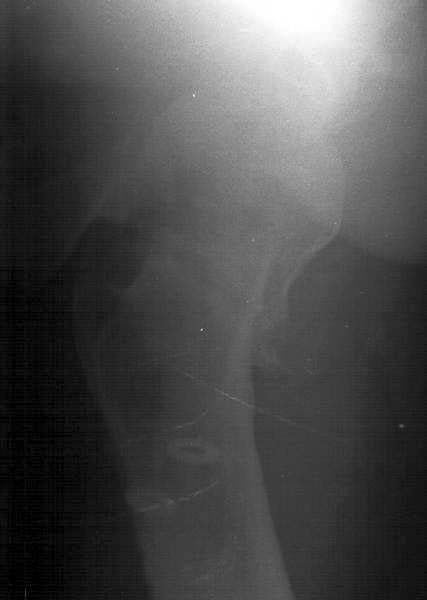

A male (32 y.o, 175 cm, 65 kg) after a car accident 1 year ago sustained a femoral neck fracture. The fracture was fixed elsewhere by cancellous screws. He noted telescoping of the screws four month later. Recently the screws have been removed. Walks with cane and marks hip pain. Xrays and CT (see attachment) demonstrate pseudarthrosis of the neck.

In a 32 year old male with a femoral neck nonunion, his best option is probably a valgus producing intertrochanteric osteotomy with blade plate fixation. In the preoperative planning stage, neutral rotation (patella up) 100% films of both hips are necessary. The AP film enclosed is with significant external rotation given the appearance of the lesser trochanter. It doesn't appear that there is significant retroversion based on the CT scan. Depending upon what his neck shaft angle is compared with his normal side, a better recommendation of the degree of osteotomy can be made. Predictable results (ie union) can be obtained without trying to reproduce a fracture angle of 25 degrees. That is, a 20 or 30 degree valgus producing intertrochanteric osteotomy with a 110 degree or 120 degree blade plate, respectively, should give a reliable result. According to the preoperartive plan with comparison to the contralateral hip in the same rotation, the lateralization of the shaft can be accomplished to help minimize proximal deformity and lateral compartment overload of the knee (theoretically). Length can be simultaneously gained as well.